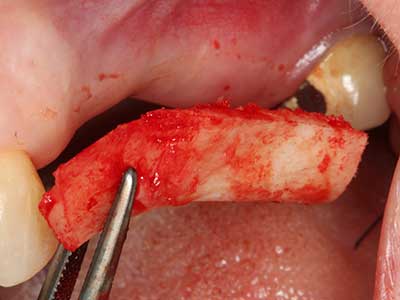

Fig. 4: Additional autologous bone chips are harvested with the bone scaler.

Fig. 5: Checking the block size at the recipient site.